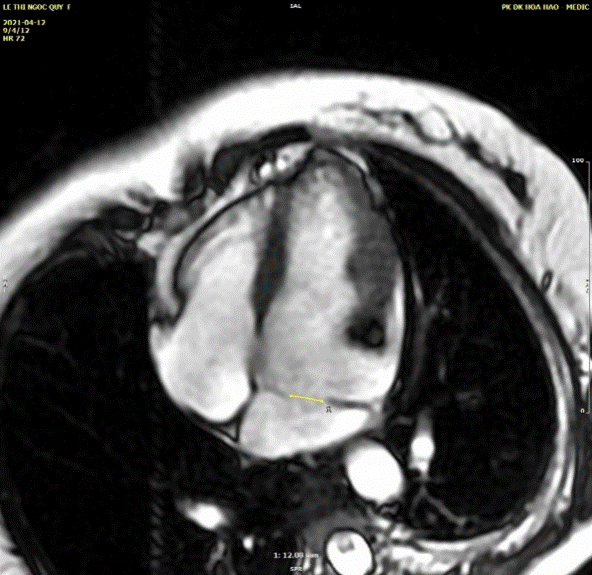

CMR

Cardiac magnetic resonance imaging (Cardiac MRI or CMR) is an advanced non-invasive technology for assessment the structure and the function of the heart. CMR in our centre was performed on GE Explorer 1.5Tesla machine, QVI 4.2 software without IV Gadovist for this case.

Cine MRI is the most valuable imaging method to determine the thickening of walls, the sizes of cavities as well as detect the abnormal structure. The steady state free precession ( SSFP ) was used to acquire the images: HLA ( horizontal long axis ),  VLA ( vertical long axis ), and the LVOT planes (Figures 13-16)

Figure 13. HLA cine SSFP sequence showed the membrane partitioned the LA into two compartments. proximal accessory & the distal true LA. The diameter of memebranous opening is as many as 12mm

Figure 14. The vertical long axis cine SSFP sequence visualized a thin membrane (arrow) with a large opening of 12mm in diameter between the edge of diaphragm and posterior wall of LA

Figure 15. The VLA cine-SSFP view was used to measure the fenestration size, the distance between membrane and mitral annulus.

CMR is a non invasive and advanced diagnostic modality due to high spatial resolution, perfect tissue contrast and non-limited  studied view . Cine MRI or steady state free precession ( SSFP ) was used to acquire the images as HLA ( horizontal long axis ),  VLA ( vertical long axis ), and the LVOT planes. We used only SSFP sequence without IV Gadolinium to depict the deviding membrane and illustrate the flow across the opening ( video 2  and 3 ). Phase-contrast sequences were not performed here to assess  the degree of obstruction because of the large opening and low pick velocity of flow across the membrane on TEE.

Cine MRI clearly depict the fenestration within membrane with the associated flow turbulence seen as a low intensity signal contrasted with the high-signal intensity of normal blood flow. CMR allows accurate assessment of chamber size and cardiac function, and it can detect also any associated anomalies [13-18].